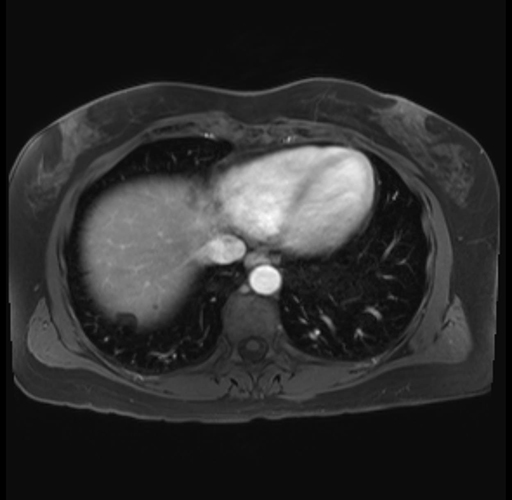

Imaging Analysis

Look through the patient's CT scan to identify any areas of concern for the necessary procedure.

Based on your CT findings, which issue(s) are present and would give reason for "planned slowing down moment(s)" in this case?

Considering a standard distal pancreatectomy procedure, what step(s) of the operation would you do differently in this case?